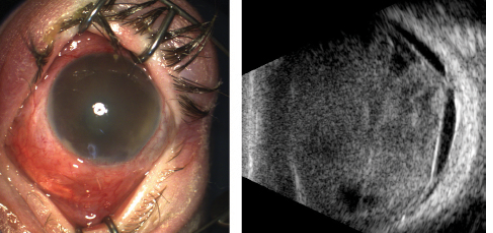

Over the next 15 months, multiple injections were required as the retinal detachment waxed and waned but never completely resolved. Then, approximately 6 weeks after the last intravitreal injection, the child developed redness of the eye, lid swelling, and decreased oral intake. EUA revealed intact conjunctiva and hypopyon in the anterior chamber. The patient was diagnosed with severe endophthalmitis (Figure 4). Vitreous biopsy was performed and intravitreal antibiotic injections were given, and the culture was negative. Over the following 2 months, the retina became totally detached, and the eye was chronically inflamed and painful. The eye was enucleated shortly thereafter.

Figure 4. Color anterior segment photograph and echographic images demonstrate turbid aqueous and hypopyon in the anterior chamber. The vitreous was filled with debris with extensive membrane formation.